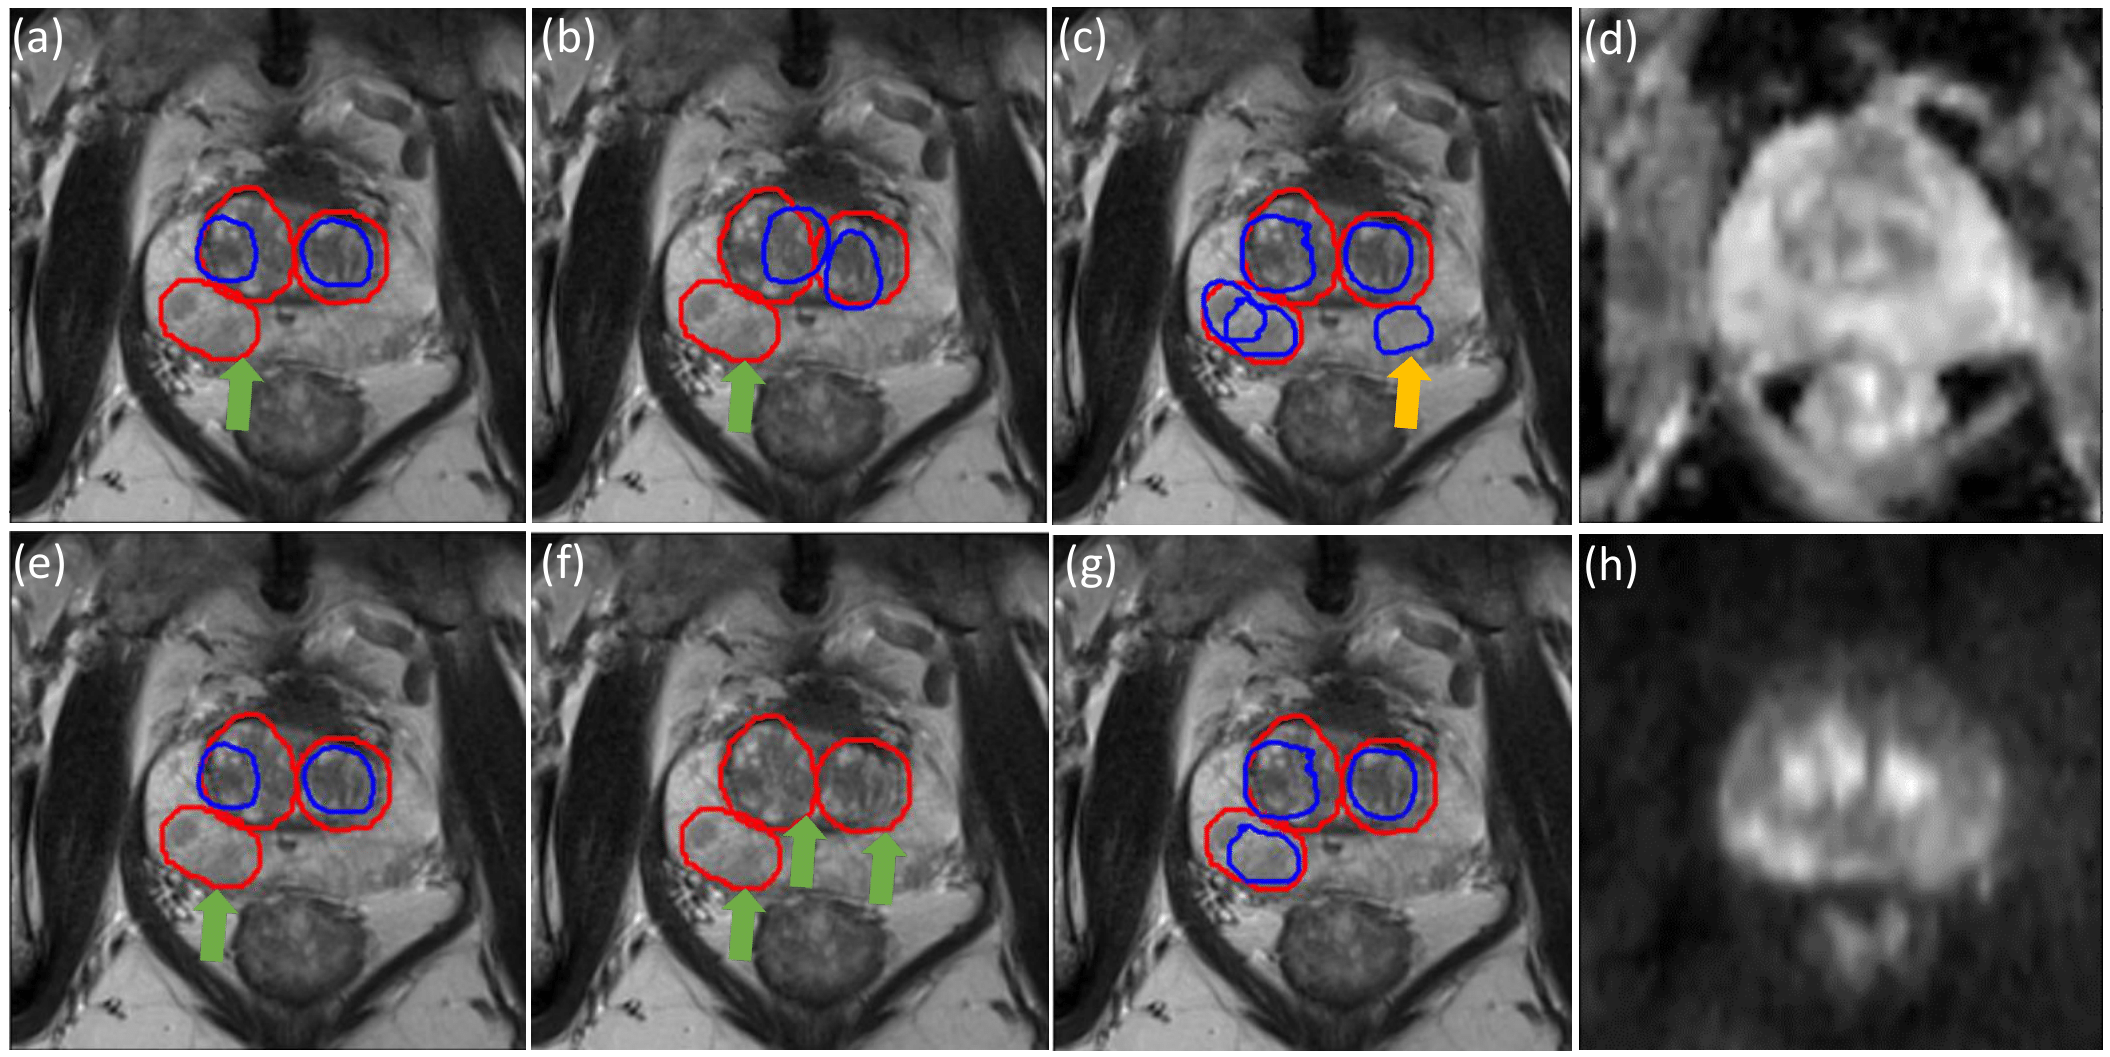

Figure 2: In all figures in this paper, (1) the red circles denote the ground-truth (GT) lesion region, while the blue circles denote the predicted regions of interest; (2) a false positive (FP) predicted detection is denoted with the yellow arrow, while another false negative (FN) lesion is denoted with the green arrow. In this study, only the lesion-level classification loss Lcost_clssubscript𝐿𝑐𝑜𝑠𝑡_𝑐𝑙𝑠L_{cost\_cls} in the training process. All example sub-figures shown here correspond to the performances on one same slice in the test data set. In the first row, threshold=0.7 while threshold=0.95 in the second row. The first three columns from the left show the detected results with only Lcost_clssubscript𝐿𝑐𝑜𝑠𝑡_𝑐𝑙𝑠L_{cost\_cls} incorporated into the training loss. (a,e) αlesion=1,βlesion=1formulae-sequencesubscript𝛼𝑙𝑒𝑠𝑖𝑜𝑛1subscript𝛽𝑙𝑒𝑠𝑖𝑜𝑛1\alpha_{lesion}=1,\beta_{lesion}=1; (b,f) αlesion=1,βlesion=3formulae-sequencesubscript𝛼𝑙𝑒𝑠𝑖𝑜𝑛1subscript𝛽𝑙𝑒𝑠𝑖𝑜𝑛3\alpha_{lesion}=1,\beta_{lesion}=3; (c,g) αlesion=3,βlesion=1formulae-sequencesubscript𝛼𝑙𝑒𝑠𝑖𝑜𝑛3subscript𝛽𝑙𝑒𝑠𝑖𝑜𝑛1\alpha_{lesion}=3,\beta_{lesion}=1. (d) Apparent Diffusion Coefficient (ADC) image; (h) Diffusion-Weighted Images (DWI) b-2000 image.

Fig. 2 shows the examples where the FNs were reduced with αlesion=3subscript𝛼𝑙𝑒𝑠𝑖𝑜𝑛3\alpha_{lesion}=3, βlesion=1subscript𝛽𝑙𝑒𝑠𝑖𝑜𝑛1\beta_{lesion}=1, by comparing Fig. 2 (c) with Fig. 2. (a,b), and comparing Fig. 2 (g) with Fig. 2 (e,f). By comparing Fig. 2 (g) with Fig. 2 (c), the FP was reduced with a higher threshold. In contrast, more FNs can be found with larger threshold and αlesion=1,βlesion=3formulae-sequencesubscript𝛼𝑙𝑒𝑠𝑖𝑜𝑛1subscript𝛽𝑙𝑒𝑠𝑖𝑜𝑛3\alpha_{lesion}=1,\beta_{lesion}=3 by comparing Fig. 2 (f) with Fig. 2 (b).